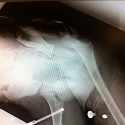

Un équivalent de Galeazzi chez l’enfant: une entité clinique rare

Mechchat Atif, Abdelmajid Elmrini

PAMJ. 2014; 19: 295. Published 17 November 2014